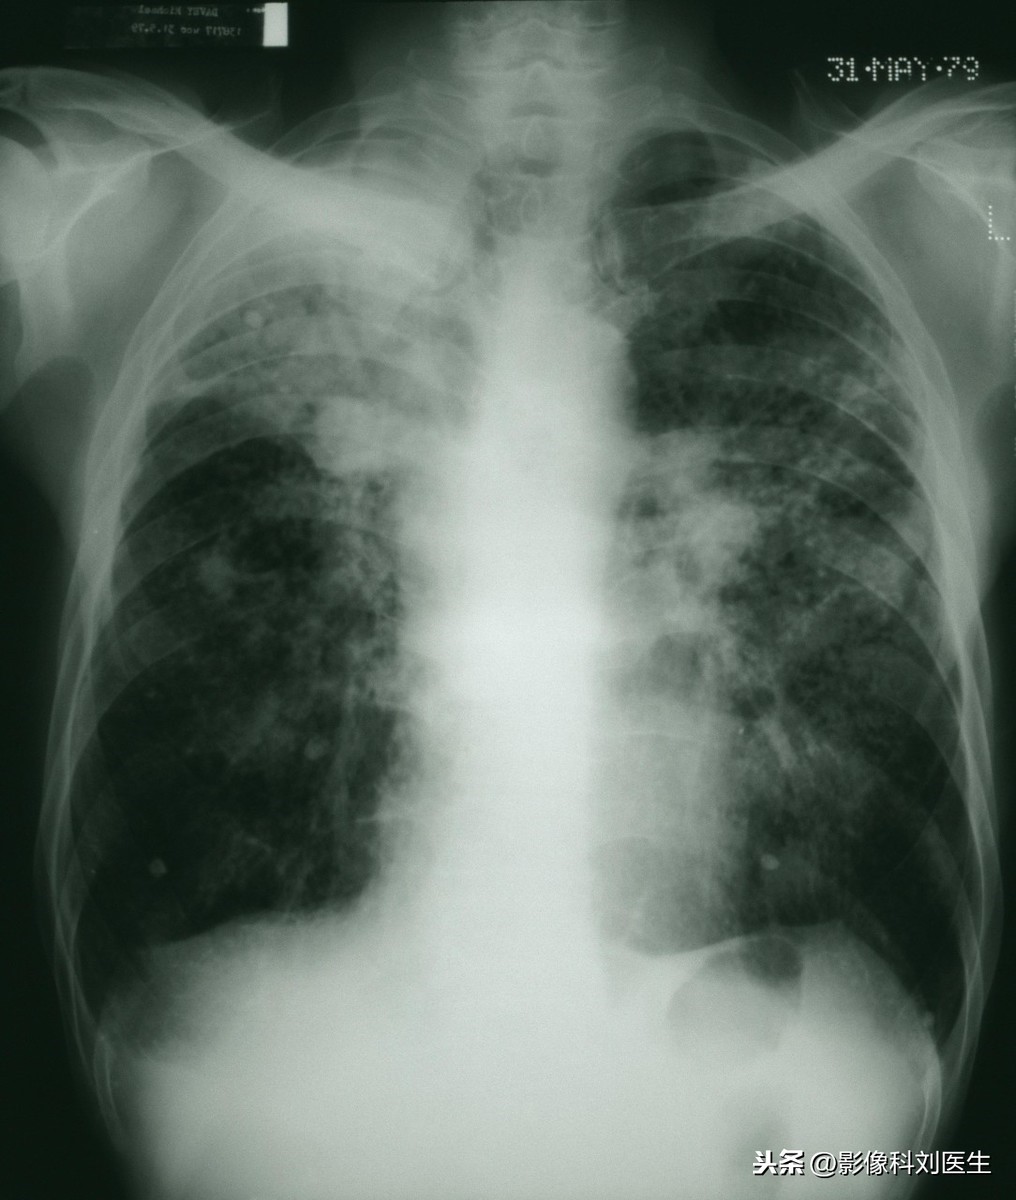

家住龙岩市的王先生便是肺部咳出煤球的主角,王先生是一个年近四十的煤矿工,而这“煤球”是王先生在一次做胸透时发现的,这球状物质是所吸入身体之中的灰尘长年累月积累下来所形成的,一种煤炭粉尘和肺部良性增生组织的混合物。

在随后的治疗之中,王先生的身体之中排出了许多的黑色物质,其中小黑疙瘩是煤尘,团状物质是肺部上皮细胞经外来的煤尘刺激,产生的良性代偿性增生。就是这些东西在王先生的身体之中危害着王先生的身体健康!

这种疾病有着自己的名字,它在医学之中叫做“煤尘肺”,在生活之中,许多人都会患上这类似“煤尘肺”这种肺部疾病!如教师易患“粉尘肺”,棉花厂的员工易患“棉尘肺”,这些肺部疾病都有着一个同一的名称——尘肺病!

这种疾病要是不及时的治疗对于肺部的危害十分的大,甚至随着时间的推移,肺脏之中的灰尘越积越多,还会导致我们的肺脏出现衰竭的显现,这时因为这种疾病丢了性命也不是没有可能的!